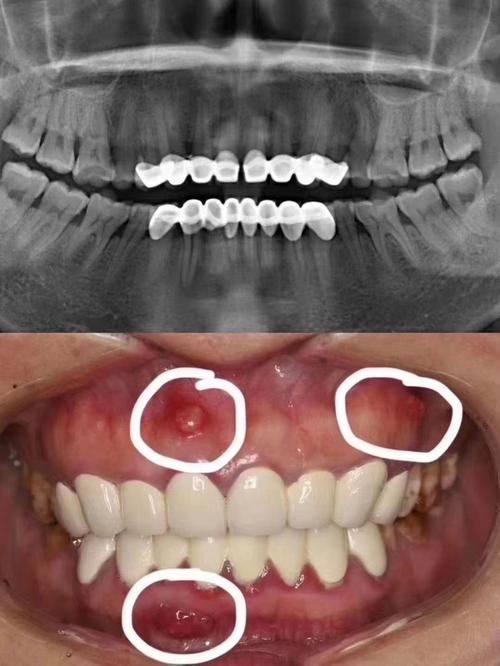

12. 口腔全景片:100 - 300元

16. 牙周治疗:1000 - 3000元